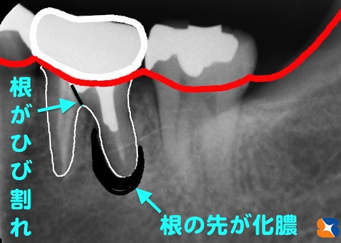

①30代の男性。主訴は「他で神経をぬいてもらった奥歯が、噛むと痛い」でした。レントゲンでチェックすると、根の先の周辺に黒い陰があるため、化膿していることが判明。